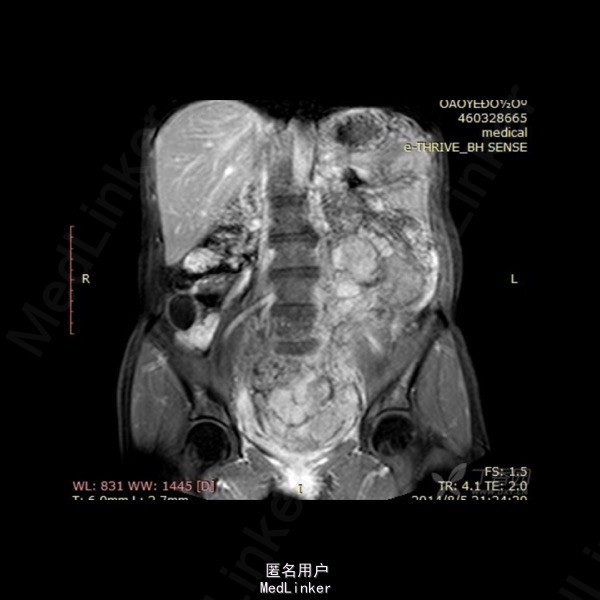

影像表现:左侧附件区示一巨大的病变,呈长T1长T2异常信号影,期内多发分隔,增强后呈不均匀强化,强化较明显。DWI示低信号。总的来看,病变为一个巨大肿块,内有分隔,境界较清。 诊断:我认为首选左侧阔韧带子宫肌瘤可能性大。由于其短期内增大,不除外瘤内出血的可能。 转于:丁香园